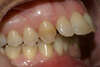

Cas Clinique d'orthodontie linguale, typologie classe II division 1

Vues avant le traitement